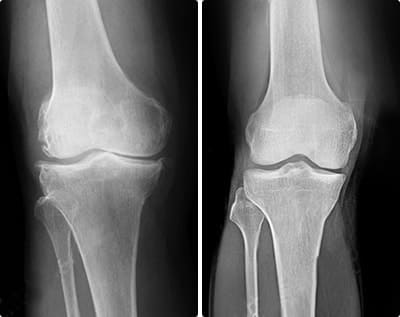

Las lesiones pueden variar en complejidad, pero se pueden agrupar en dos tipos: musculares y articulares. Esguinces, desgarros, osteoartritis crónica. Los riesgos son inevitables si no te proteges a tiempo.